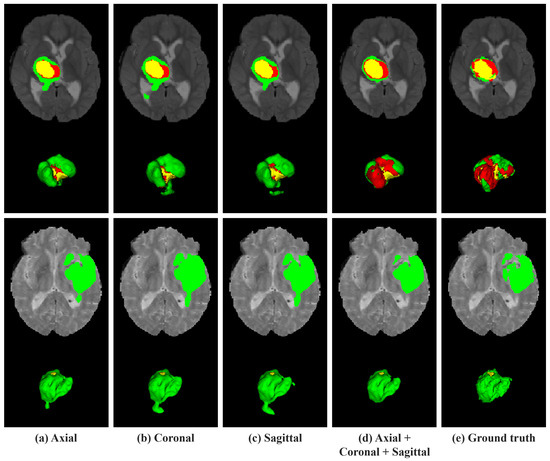

4.5.3. Effectiveness of MultiScale Contextual Fusion Module

The third ablation study was conducted to demonstrate the efficacy of MSCF in harnessing the complexity and variability of tumor sizes, as well as their spatial distribution across MRI data. Inspired by the ASPP and CFP, the MSCF module implements a hybrid approach that encapsulates contextual information across various scales and achieves a synergistic effect. The ASPP aspect of MSCF utilizes a series of dilation rates to extract features from a broad range of receptive fields without compromising resolution. Concurrently, CFP introduces a sequence of dilation rates designed to progressively capture larger contextual features, thereby enhancing the network’s spatial discernment across scales. Table 5 presents the comparative analysis results for the BraTS 2020 validation dataset, focusing on the performance of the MSCF module, with the best scores highlighted in bold. The superiority of Full MSCF, which achieved the highest Dice scores and lowest Hausdorff distances when all components were integrated, is clearly demonstrated. These improvements are crucial because the Full MSCF module ensures a comprehensive representation of the spatial and contextual nuances essential for accurately delineating tumor boundaries.

Figure 9 presents a visual comparison of the tumor segmentation outputs across various MSCF configurations on the BraTS 2020 dataset. From left to right, each column represents the MSCF without the ASPP component (MSCF w/o ASPP), MSCF without the CFP component (MSCF w/o CFP), Full MSCF with all components integrated, and the ground truth for comparison. In the visualization results, the performance in the NCR/NET regions, marked in red, was inaccurately predicted by all models except Full MSCF. Specifically, in the first row, the MSCF without the ASPP component failed to accurately predict the NCR/NET regions that matched the actual values. Moreover, the MSCF without the CFP component predicted only a small portion of this region. Additionally, in the second row, the same slices reveal that both MSCF without the ASPP component and MSCF without CFP component failed to predict the NCR/NET regions. These outcomes were further confirmed through 3D-rendered visualization results. While the Full MSCF predicts NCR/NET regions that closely resemble that of the ground truth, both the MSCF without the ASPP component and the MSCF without the CFP component failed to accurately predict the NCR/NET regions.

Figure 9.

Visual comparison of MSCF module variations for tumor segmentation on the BraTS 2020 dataset. The colors indicate regions of tumors. Red: NCR/NET; yellow: ET; green: ED.